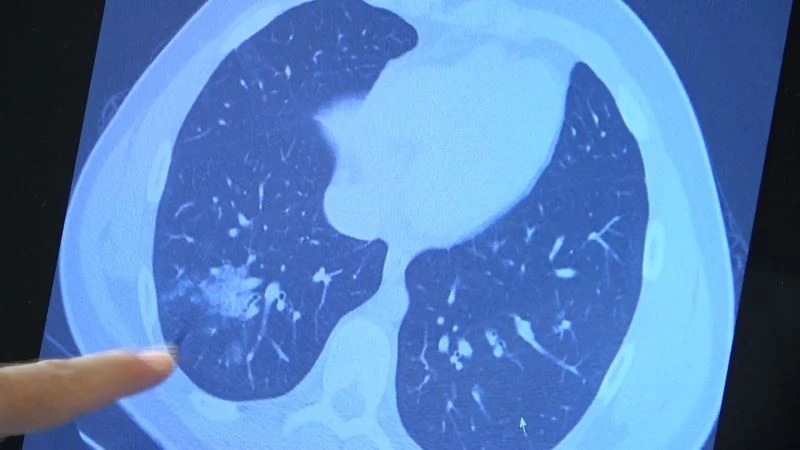

Korona virüste aşılama yaşı her geçen gün düşerken aşı olmayan çocuklarda da ciddi akciğer tutulumları görülmeye başladı. 12 yaş üzeri kronik rahatsızlığı olan hastalara artık aşılama yapılabiliyor. Göğüs Hastalıkları Uzm. Prof. Dr. Şevket Özkaya ise aşı olmamış kronik rahatsızlığı olan 14 yaşındaki bir çocuğun akciğerlerinde oluşan ciddi tahribatı gözler önüne serdi.

Bazı vatandaşlar hâlâ aşı olmakta tereddüt etmeye devam ederken korona virüs çocuk grubundaki hastaları da etkilemeye başladı. VM Medical Park Samsun Hastanesi Göğüs Hastalıkları Kliniği’nden Prof. Dr. Şevket Özkaya ise aşı olabilecek yaş grubundaki çocukların bir an önce aşılanması gerektiğine vurgu yaptı. 14 yaşında, kronik rahatsızlığı olan ve akciğerlerinde tahribattan dolayı ciddi öksürük, ateş ve nefes darlığı çeken bir hastanın akciğerlerini inceleyen Prof. Dr. Özkaya, "14 yaşındaki kronik rahatsızlığı mevcut olan bir genç hastamızda ciddi akciğer tutulumları var. Her iki akciğerinde de yaygın buzlu cam ve konsolidasyon alanları var. Bu yaştaki çocuklarda beklemediğimiz bir durumdur. Okullarımızda da bu risk var. Okullarımızın açık kalmasının ve sağlık sistemimizin kitlenmemesi için mutlaka aşı olmalıyız. Çocuklarımıza rol model olmalıyız. Şu anda hastanelerimiz hastalara yetişebiliyor. Yatak sayımız yeterli. Ancak kontrollü sosyal hayatımızı düzene sokmadıkça ve aşı olmadıkça, gelecekte hastanelerde yatak sayısı sıkıntısı çekebiliriz" dedi.

Okulların açılmasıyla ailelerin çocuklarını nasıl salgından koruyacakları konusunda tereddütlerinin başlayacağını ifade eden Prof. Dr. Özkaya, "Aşıda yaş grupları düştükçe, hastalık aşı olmayan yaş gruplarında görülmeye başladı. Artık 15-18 yaşlarında aşılarını olmamış hastalarımız da ciddi akciğer tutulumları ile hastaneye gelebiliyorlar. Çocuklarımıza maalesef kötü örnek olduk. Maske, mesafe ve kontrollü sosyal hayatımızı tam doğru olarak gerçekleştiremedik. Bunları okullarda çocuklardan istememiz çok zor olacak. Çocuklarımızı korumanın birinci yolu aşıdır. Mutlaka aşı yaşı gelmiş her öğrencimizin aşı olması gerekiyor. Aşı çağı gelmemiş çocuklarımızın ise özellikle ailesinde anne, baba ve daha büyük ebeveynlerinin, anneannelerin, dedelerin aşılanması gerekiyor. Çocuklara rol model olmamız gerekiyor. Maske, mesafe, temizlik felsefesini çocuklara örnek olarak göstermeliyiz. Okulların açık kalması iki koşula bağlıdır. Birincisi aşı yaşına gelmiş çocuklarımızın aşılanmalarıdır. İkincisi aşı yaşına gelmemiş çocukların büyüklerinin aşılanmalarıdır" diye konuştu.